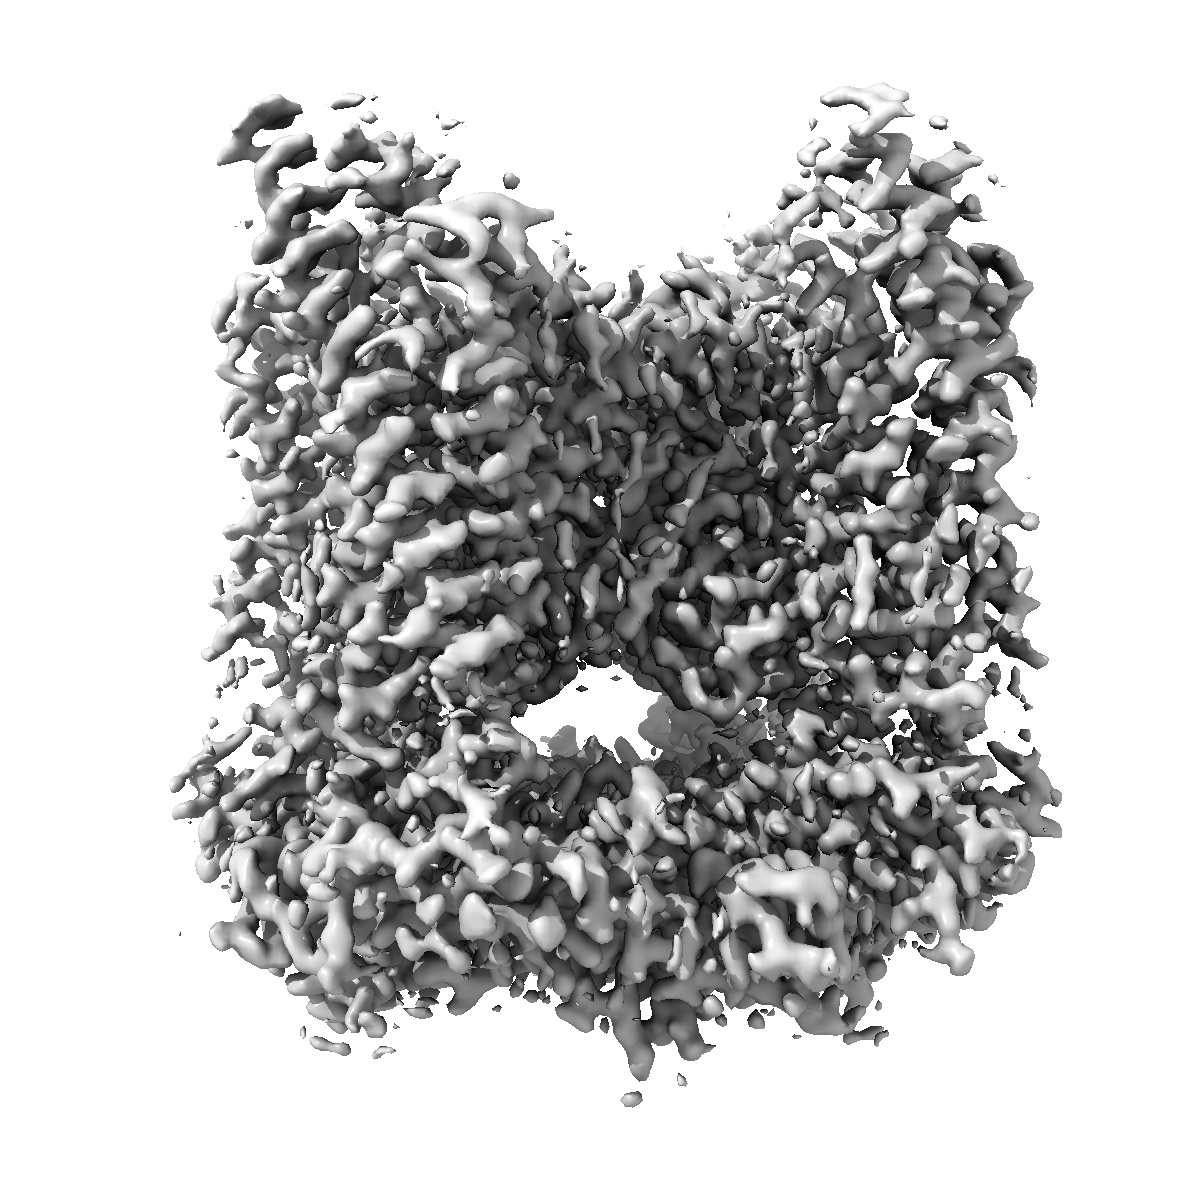

TRPML1 in complex with compound 5

EMD-52211

Single-particle2.1 Å

Sample: Mucolipin-1

High throughput cryo-EM provides structural understanding for modulators of the lysosomal ion channel TRPML1.